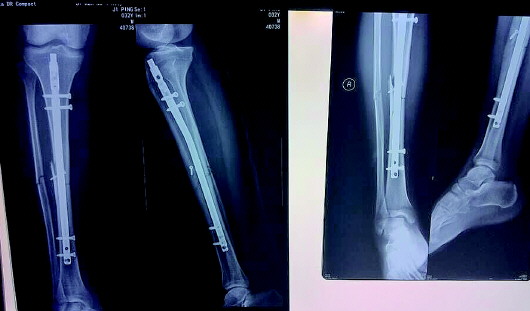

从CT片可以明显看出,在同一部位,患者8月19日(左图)出院时受伤部位还没有纱布,而9月11日(右图)再回到医院时就出现了纱布(阴影部位)。 本报记者 戚云雷 摄